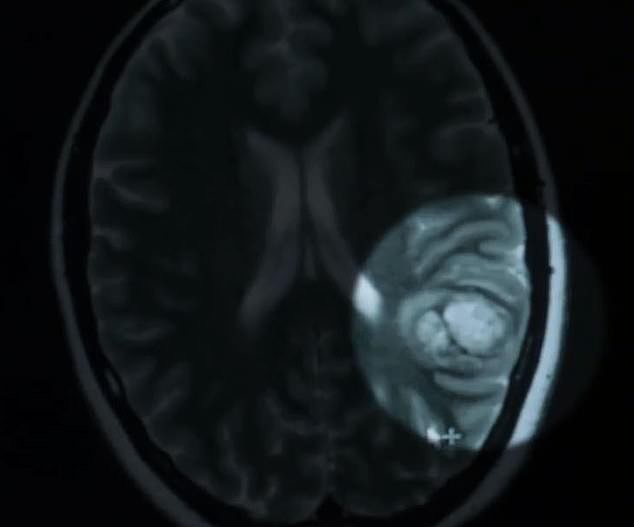

Khối u máu của Schardt nằm ở bán cầu não trái, nơi xử lý 95% khả năng sử dụng ngôn ngữ của cô. Ước tính cứ 100-200 người thì sẽ có một người mắc u máu não, nhưng một phần tư trong số họ không hề có bất cứ triệu chứng nào biểu hiện ra bên ngoài.

Khối u máu trong não Schardt